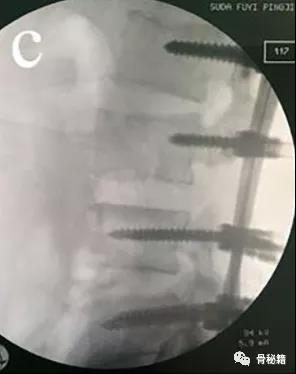

1、远端植入椎弓根螺钉,保留一些距离2、近端植入到底的椎弓根螺钉

3、若存在左右侧的位移,可让螺钉的开口侧面向近端脱位的一侧4、将棒塑性有一些弧度,先锁定远端后,利用棒的弹性来逐渐锁定近端达到复位

5、然后再将远端的钉子与棒逐个分离后拧入适当的深度,最后更换更合适的棒进行锁定